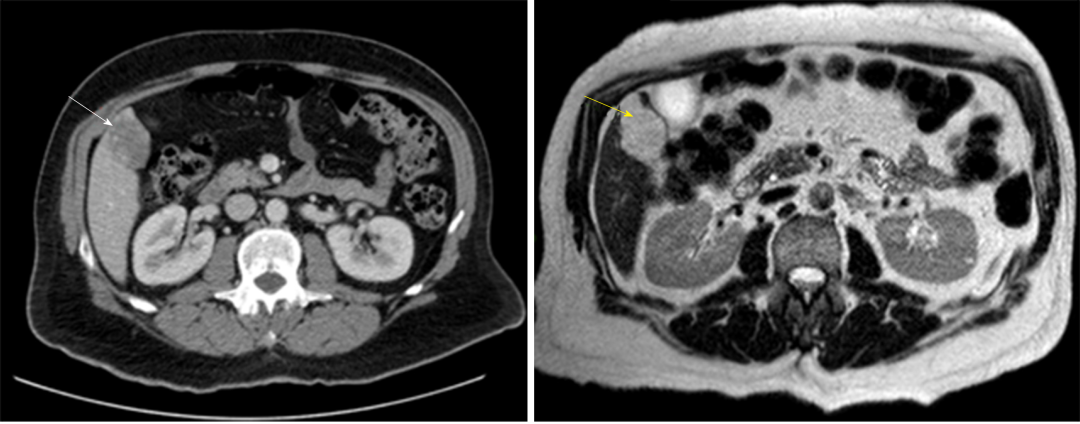

诊断:HH的诊断目前主要依赖于影像学检查,多种检查手段联合应用可提高诊断准确率。常规首选超声检查,再结合CT、MRI以及数字减影血管造影检查等综合判断。

图3 腹部CT造影(白色箭头)和MRI T2加权扫描(黄色箭头)